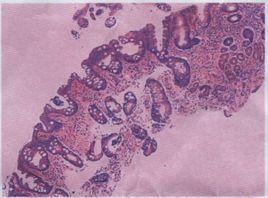

胃萎縮又叫A型胃炎。是萎縮性胃炎一種,萎縮性胃炎分為A、B型

胃萎縮胃炎。萎縮胃炎是慢性胃炎的一種。A型胃炎主要是胃部平滑肌瀰漫萎縮,其發病機制與自身免疫有關。